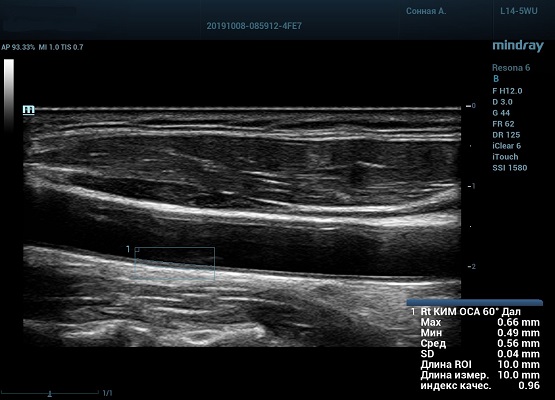

На сегодняшний день измерение IMT происходит автоматическим путем при использовании функции AUTO-IMT. Необходимо указать прибору зону интереса, стандартной длиной (1 см), в которой происходит отслеживание кромок и выдача максимального, среднего и минимального значения.

УЗИ аппараты компании Mindray среднего, экспертного и премиального класса снабжены данной функцией и позволяют контролировать не только полученные значения, но и оценить точность измерения кромки в конкретной зоне по индексу качества. Используя индекс качества, легко решить, можно ли использовать полученное значение.